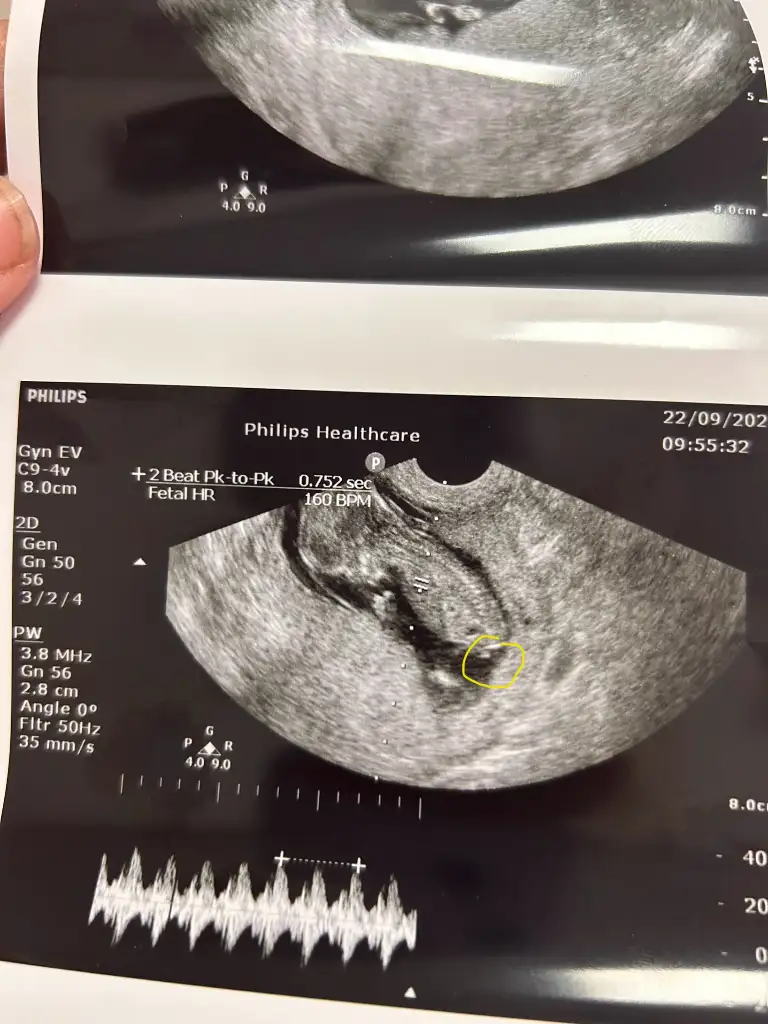

Chat gpt şu ultrason görüntüsüne bile kız dedi bebeğim erkek doğru tahmin edemiyorBenim de yapay zekalar kız diyor detaylıda mı belli oldu fotoğraf varsa atar mısınız çok merak ettim. Bir de özel hastane miydi ve doktorunuz tecrübeli miydi

Nubu nasıldı canım kız mı demişlerdi önceChat gpt şu ultrason görüntüsüne bile kız dedi bebeğim erkek doğru tahmin edemiyor Eki Görüntüle 3649931

Yok doktor en başından beri erkek dedi 13. Haftada öğrendim ama chat gpt kız diyordu yani doğru tahminde bulunmuyor onu söylemek istedim. Sizin bebiş bana kız gibi geldi amaNubu nasıldı canım kız mı demişlerdi önce